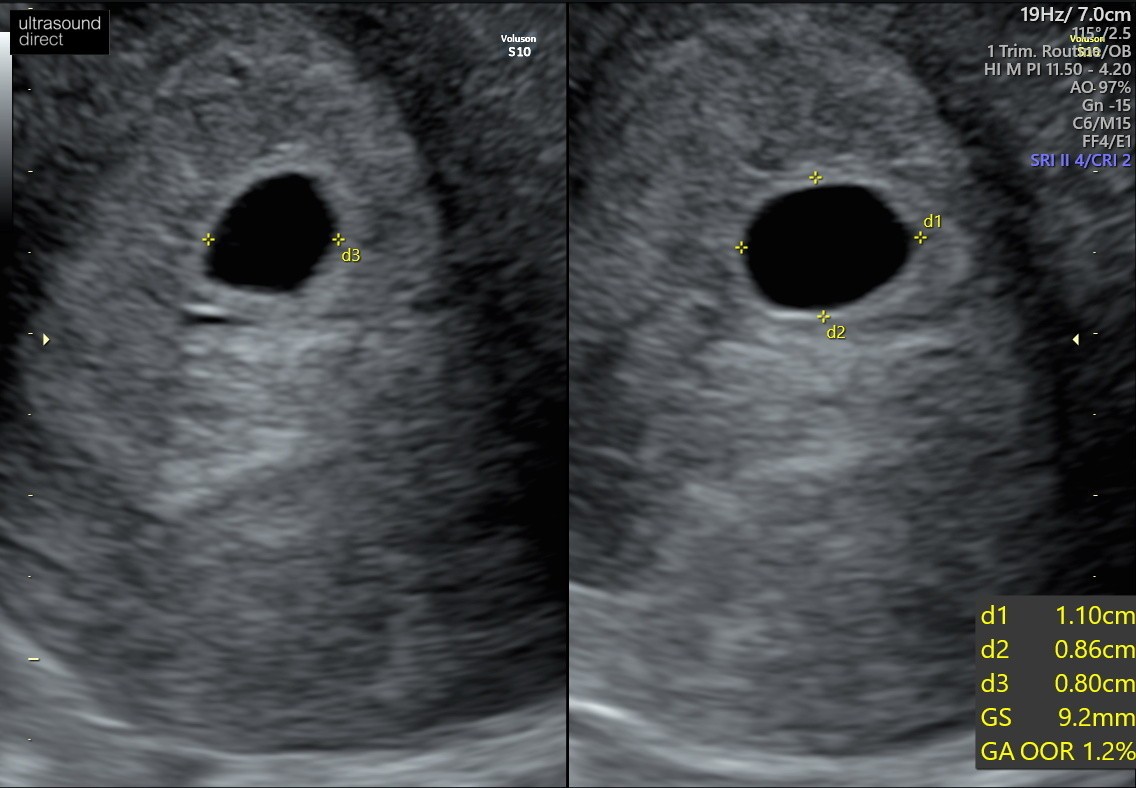

Ostatnia miesiączka 30 maj. Cykle ~32 dni. Z usg około 7 tydzień z kawałkiem. Byłam 22 lutego na usg - puste jajo płodowe. Pęcherzyk 1,78cm. Beta hcg ponad 50.000. Dostałam skierowanie do szpitala i tutaj moje pytanie - czy mam czekać? Jest szansa, że zarodek jeszcze się pojawi? Czy już nie robić sobie nadziei? Nie mam żadnych plamień ani krwawień, a czytałam dużo historii, że zarodek pojawił się w późniejszym czasie.